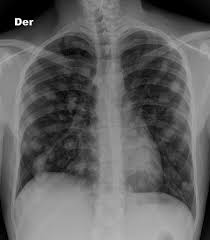

How To Know If Testicular Cancer Has Spread To Lungs / Orchid Results : Lump or swelling in your neck, under your arm, or in your groin.. This is not lung cancer. If testicular cancer has spread to other parts of your body, you may also experience other symptoms. When testicular cancer spreads, it most commonly spreads to the lung and the lymph nodes of the chest, pelvis, and the base of the neck. It's not called lung cancer unless it starts from cells in the lung. Good prognosis means that your primary cancer was in your testicle, or at the back of your stomach or abdomen (retroperitoneal).

The best way to confirm the diagnosis of testicular cancer is to remove the testicle. As others have said this is a type of cancer which does not behave in the same way as most. Swelling and enlargement of male breasts. For example, breast cancer that spreads to the lung is called metastatic breast cancer, not lung cancer. These cancers have spread to a distant lymph node or the lungs. As with other forms of cancer, testicular cancer can spread, or metastasize, to other areas of the body. In stage 3 of the disease, the cancer has invaded other organs such as the lungs, brain or liver. This is testicular cancer which has spread to the lungs. If testicular cancer spreads, it can spread to the following: Which treatment your doctor will choose to treat it is based on the type of cancer you have and if it has spread. Cancer is always named for the place where it starts. So when testicular cancer spreads to the lung (or any other place), it's still called testicular cancer. Liver is pretty close to the lungs.

Headaches or confusion, from cancer spread in the brain. But most of the time they're on the edges of your lungs or in the lower lobes. Swelling of 1 or both legs or shortness of breath from a blood clot can be symptoms of testicular cancer. The tumour has only spread to the abdominal lymph nodes or the lungs or both. Shortness of breath, chest pain, or a cough (even coughing up blood) may develop from cancer spread in the lungs.

Prognostic Factors Of Metastatic Testicular Non Seminomatous Germ Cell Tumors After Chemotherapy Sciencedirect from ars.els-cdn.com This is not lung cancer. Lymph nodes are glands that make up your immune system. Swelling and enlargement of male breasts. The nature (cell type) of the metastatic. Shortness of breath, chronic cough or chest pain can turn out to be the symptoms of testicular cancer that have affected the lungs. As with other forms of cancer, testicular cancer can spread, or metastasize, to other areas of the body. Good prognosis means that your primary cancer was in your testicle, or at the back of your stomach or abdomen (retroperitoneal). If it is not detected and treated, testicular cancer eventually can spread to the lungs, brain, liver, and other parts of the body.

Testicular cancer begins in your testes, the male reproductive organ. Tumor marker protein levels are normal or slightly elevated. Swelling of 1 or both legs or shortness of breath from a blood clot can be symptoms of testicular cancer. Cancer can spread to any part of your lungs. There is no poor prognosis grouping for seminoma testicular cancer. Headaches or confusion, from cancer spread in the brain. Your markers are only slightly above normal (s1 in the tnm staging system). If cancer cells have spread to your lymph nodes (or beyond your lymph nodes to another part of the body), symptoms may include: Stage iii testicular cancer has three subcategories: But most of the time they're on the edges of your lungs or in the lower lobes. A blood clot in a large vein is called deep venous thrombosis or dvt. Testicular cancer is uncommon and, while it can develop at any age, it mainly occurs in men between ages 25 and 44. A lump or swelling in your neck.

Shortness of breath, chest pain, or a cough (even coughing up blood) may develop from cancer spread in the lungs. Symptoms of metastatic testicular cancer can include: Cancer that's spread to other parts of the body is known as metastatic cancer. If testicular cancer has spread to other parts of your body, you may also experience other symptoms. The best way to confirm the diagnosis of testicular cancer is to remove the testicle.